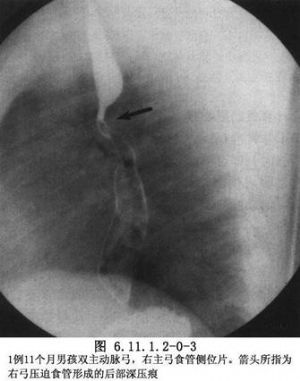

双主动脉弓影像表现见下图(图6.11.1.2-0-3,6.11.1.2-0-4)。